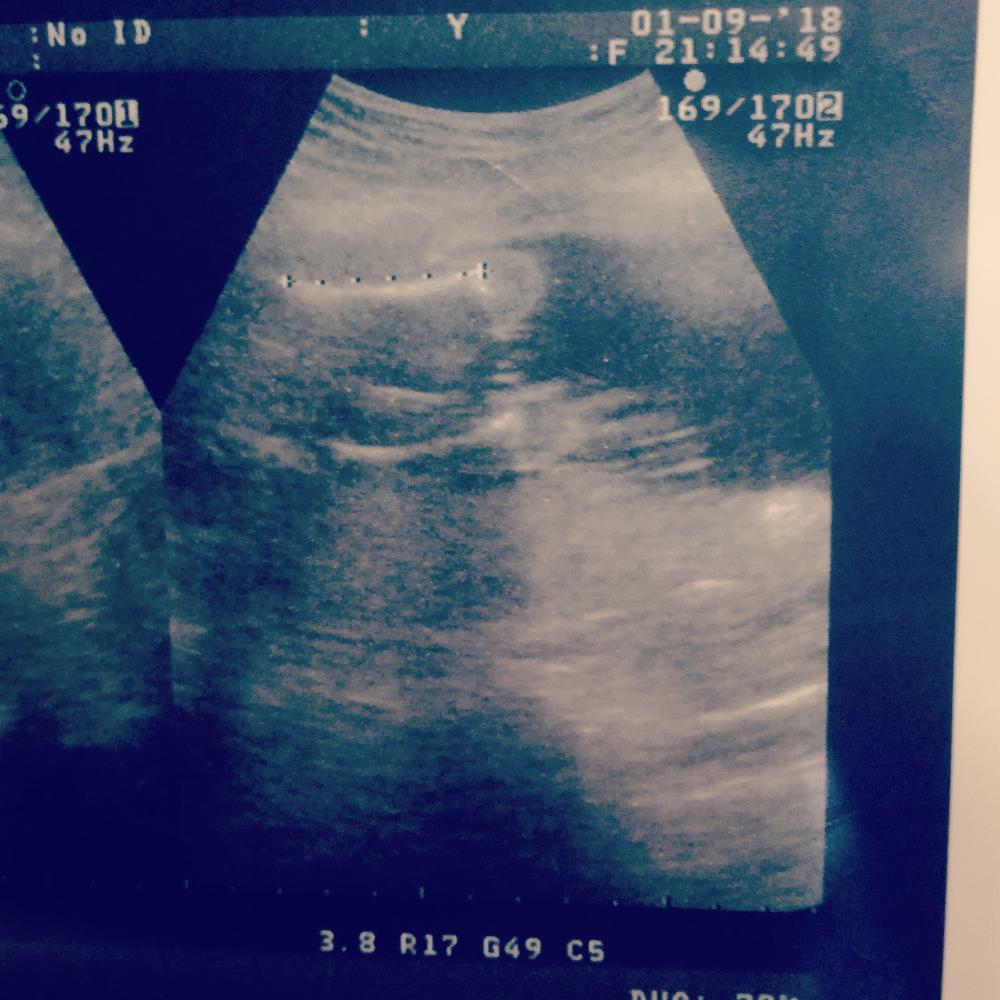

طيب الشاطره بسونار ايش اللي واضح بسوناري

سونارك اشوف عضووو واضح ماشاءالله طيب الشاطره بسونار ايش اللي واضح بسوناري

انتي شبيه سوناري

طيب بنات وش في سوناري؟